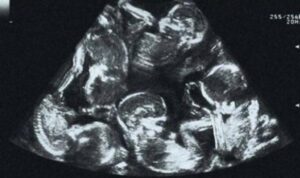

O caso a seguir, acabou tendo grande repercussão em todo país, após uma jovem, de apenas 23 anos de vida, ir até o hospital, onde fez exames a respeito de sua gravidez, onde o médico revelou que ela estaria grávida de gêmeos.

Acontece que a jovem não estaria grávida de gêmeos, e sim de um quíntuplo, sendo eles 4 meninas e 1 menino, para a surpresa de todos.

Os médicos contratam que durante os primeiros exames, não puderam notar as 5 crianças, e elas ainda ficaram bastante famosas após o nascimento, já que um caso de 5 crianças gêmeas nascerem, é quase impossível!